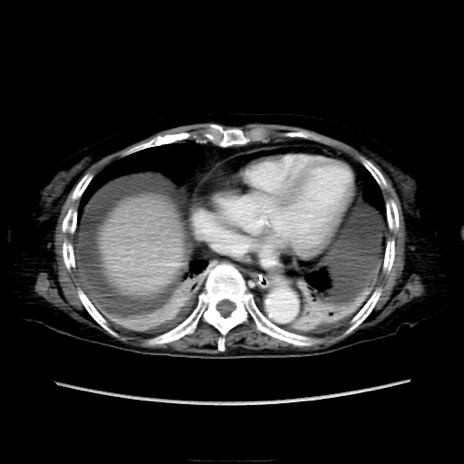

症例40(横断像)

【症例】90歳代女性

【主訴】腹痛・嘔吐

【現病歴】 食欲低下、嘔吐があり昨日他院受診。肺炎と診断され入院となる。入院後より腹部全体に圧痛あり。胃管留置され経過みていたが、症状持続するため、

当院転院となる。

【既往歴】胸椎圧迫骨折、胆石症

【身体所見】腹部:中央に激痛あり、圧痛あり、反跳痛不明

【データ】WBC 17100、CRP 18.82

横断像